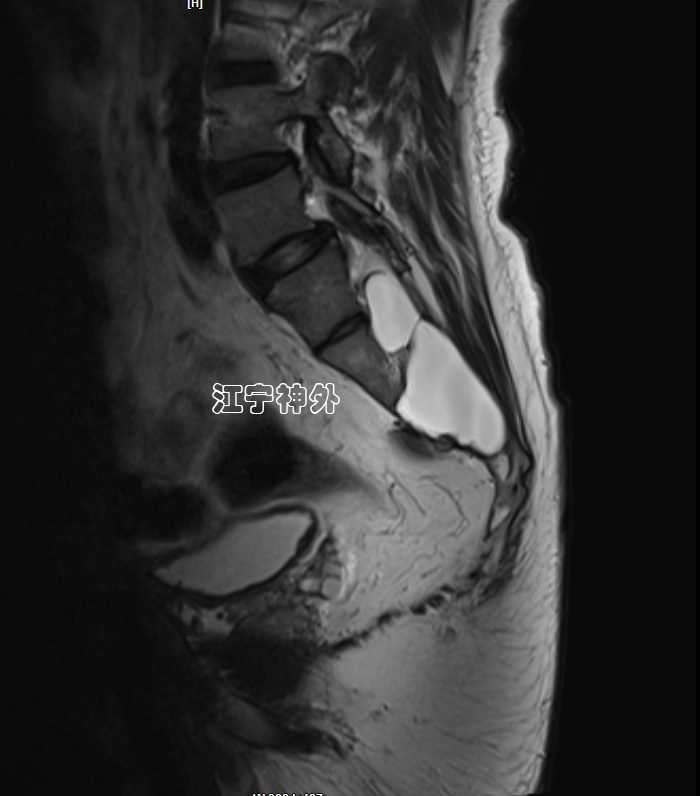

我院术前磁共振检查发现,骶1-3两个巨大骶管囊肿,其中左侧骶管囊肿更大,但症状却是在右侧。

郑主任仔细阅片发现,右侧骶管囊肿虽然比较小,但是其脑脊液漏口处(囊颈)存在一块灰色异常信号,推测可能存在神经根内疝。

正如术前所预计的一样,我们果然发现右侧骶管囊肿的漏口很大,除了本来的穿行神经根,还有两根过路的神经根呈M形疝入漏口,并且与漏口粘连严重,形成嵌顿,这也就解释了为什么右侧骶管囊肿比较小,症状却很严重。

术后磁共振显示双侧骶管囊肿封堵良好。并且使用钛板修补了缺损的骶管后壁,避免骶管内容物膨出。